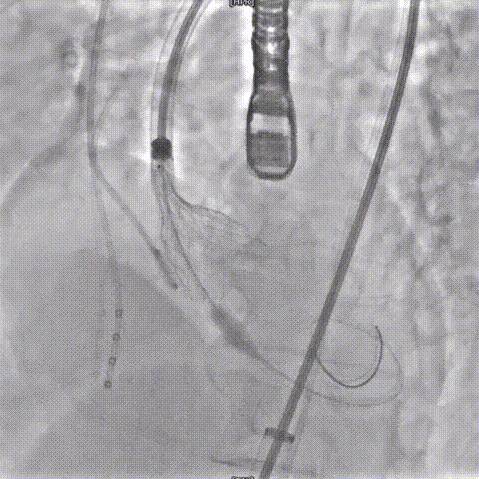

手术过程概览

主动脉根部造影

20mm球囊预扩

输送器过弓

瓣膜释放到工作位

23mm瓣膜释放

术后造影